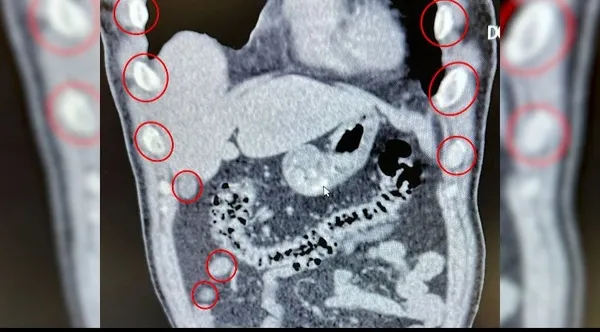

İl Emniyet Müdürlüğü Narkotik Suçlarla Mücadele Şubesi ekiplerince Tatvan'da durdurulan otobüste yolcu olarak bulunan yabancı uyruklu 2 şüpheli gözaltına alındı. Tatvan Devlet Hastanesine götürülen şahısların yapılan röntgen ve tomografi kontrollerinde mide ve bağırsaklarında çok sayıda kapsül olduğu belirlendi. Yapılan tıbbi müdahaleyle çıkarılan 136 kapsülün içerisinde toplam 1 kilo 48 gram metamfetamin bulundu. Gözaltına alınan şüpheliler, emniyetteki işlemlerinin ardından çıkarıldıkları mahkemede tutuklandı.